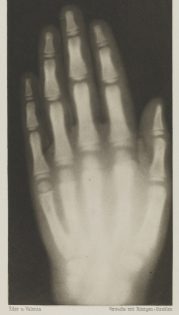

The news of Roentgen’s discovery spread quickly throughout the world. One of his first experiments late in 1895 was a film, or shadowgraph, of his wife Bertha’s hand with a ring on her finger. Of all the first pictures of his that were circulated it was that of the human hand that made the greatest impression upon the public. Everywhere people began testing the new radiation by taking pictures of the bones in their hands.

Although people were calling the new rays Roentgen rays, Roentgen named them X-rays, because in mathematics “X” is used to indicated the unknown quantity.